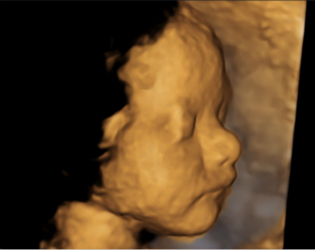

四维超声检查(动态三维超声检查)只是给宝宝拍了一张照片,对胎儿位置和姿势要求较高,胎儿孕周比较大才能拍的好,不能够评价胎儿的结构和发育情况。如果要求了解宝宝的结构是否正常,只需要选择系统产前超声检查。

点击这里看看四维彩超里的萌宝//v.qq.com/page/u/8/9/u03089v9w89.html